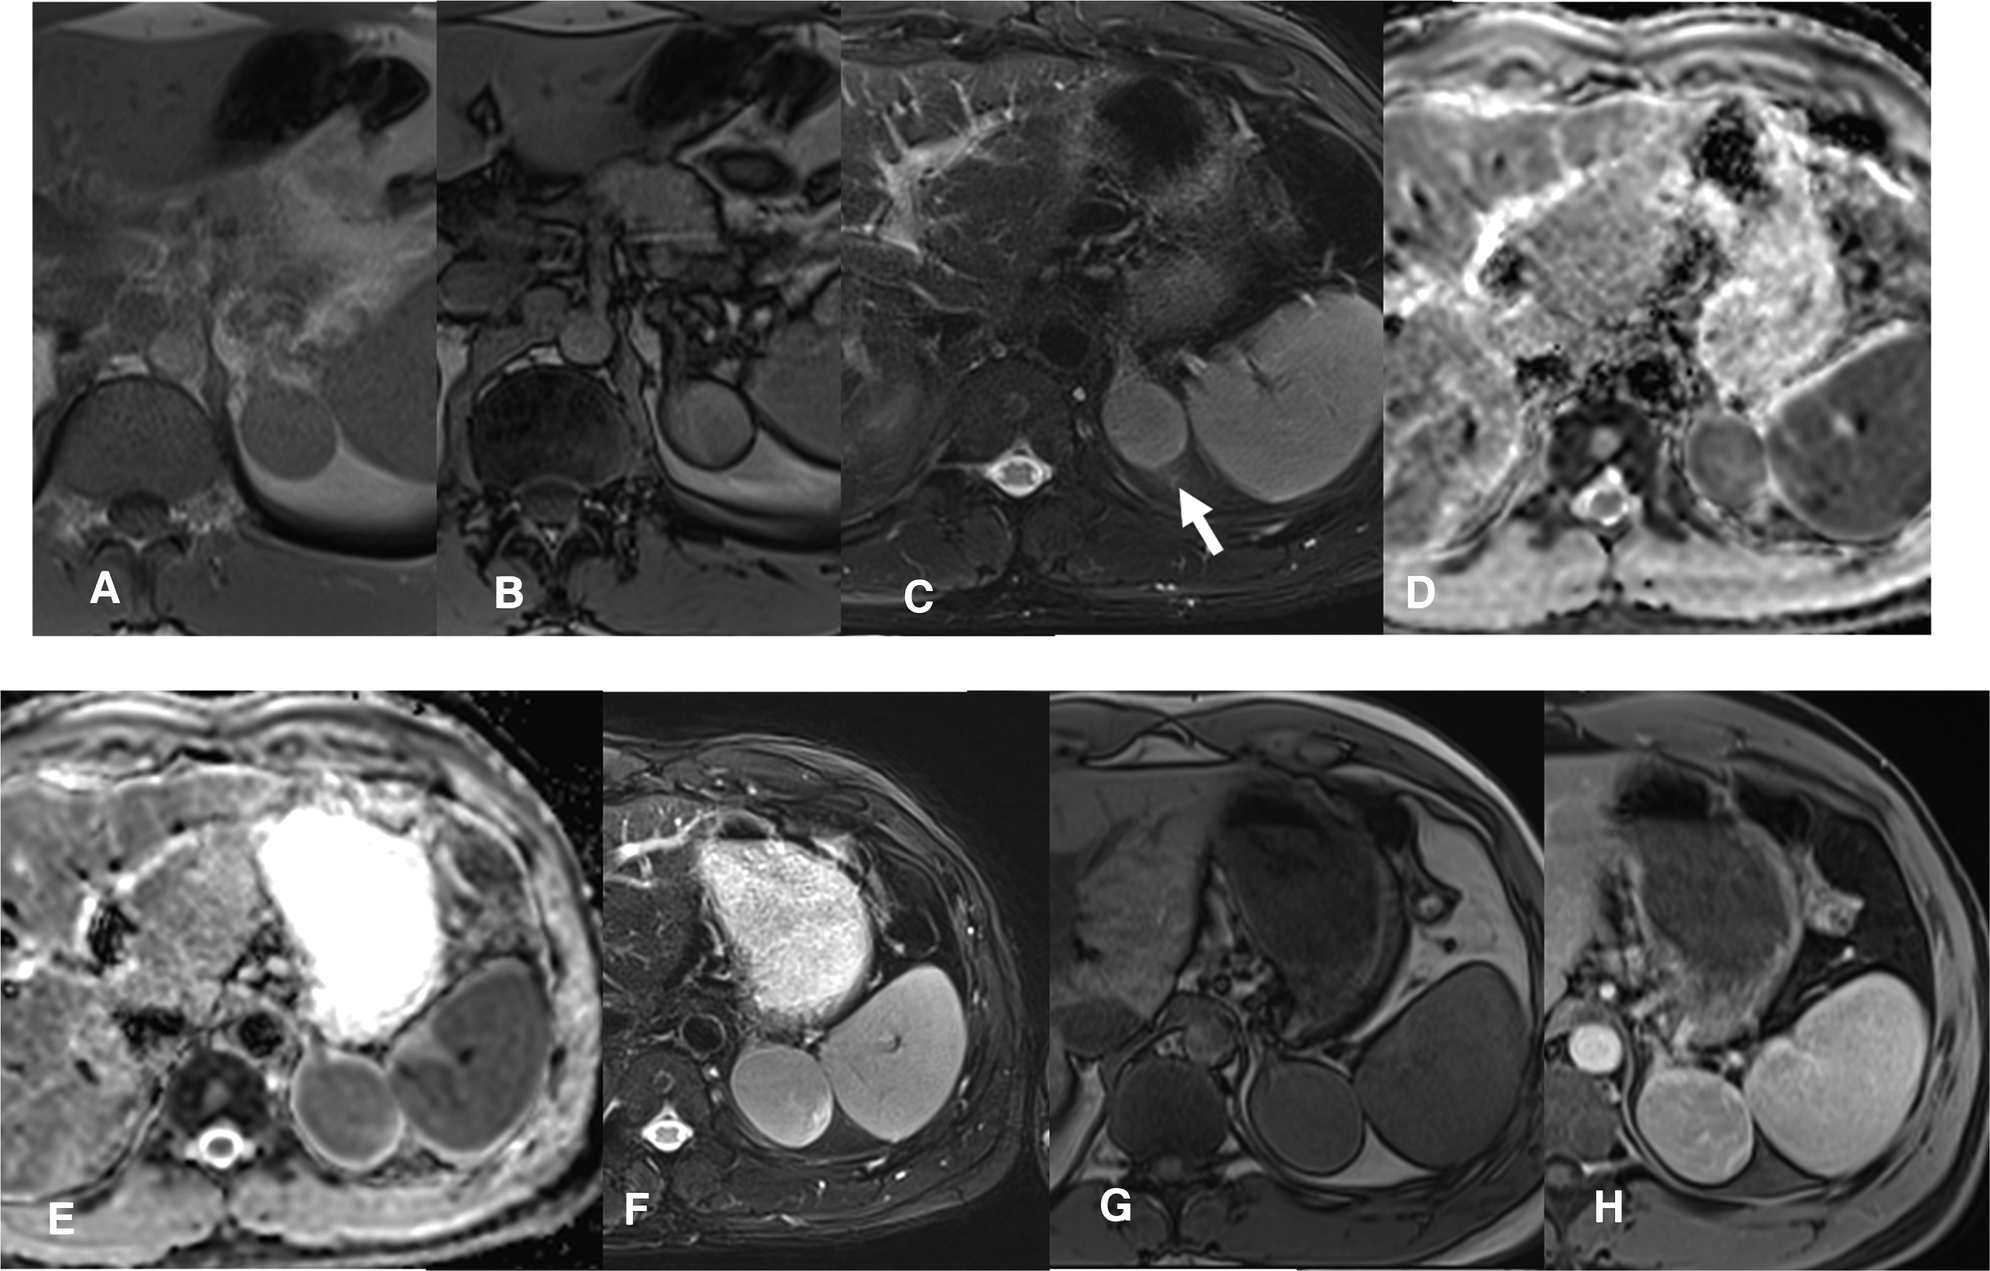

Figure 2

MRI scan 2019- Follow-up confirms the presence of a slightly enlarged, compared to the CT control, left adrenal solid mass. The T1 in-phase (IP) and out-of-phase (OOP) sequences (A,B) confirm a substantial absence of lipid content. The mass is rather homogeneous, isointense in T2 STIR (C, arrow), solid with restriction in the diffusion map (D). MRI scan 2020- A clear enlargement of the adrenal mass is present (maximum diameter about 5 cm), which is heterogeneously solid in the DWI map (E). Also in T2 w (F) the mass is larger and heterogeneous, in T1 w the mass has a parenchymal signal (G) with a slightly inhomogeneous post-contrast impregnation (H, venous phase).

A 40-year-old man was seen at our clinic in summer 2020 for a left adrenal mass. At the age of 19, he had suffered from ACTH-independent Cushing syndrome, when a right adrenal lesion was detected at CT scan, leading to adrenalectomy. Histopathology was indicative of adrenocortical adenoma. Cortisol normalization occurred after surgery and follow-up visits were scheduled, with regular assessment of adrenal function and abdomen ultrasound imaging. In 2018, a CT scan had revealed a left adrenal mass with a maximum diameter of 3 cm (Figure 1). A diagnosis of adrenocortical adenoma with low lipid content was suggested. The absence of a previous CT scan to make a comparison, the size of the mass at that time (less than 4 cm), the mass homogeneity (absence of calcifications and hemorrhagic areas), the density (30–40 HU on average, below the limit of 43 HU), the regularity of the margins and the lack of a CT delayed phase (to evaluate the wash-out) had probably orientated the diagnosis. Hormonal evaluation disclosed normal adrenal function [ACTH 29 pg/mL, serum cortisol 450 nmol/L, serum cortisol after 1 mg dexhametasone 41 nmol/L, UFC 58 mcg/24 h, renin 7.8 µU/mL, serum aldosterone 100 pg/mL, aldosterone (ng/dL)/renin (µU/mL) 1.28, urine metanephrine 25.5 µg/24 h, urine normetamephrine 105.8 µg/24 h]. At an MRI scan performed in 2019, the lesion showed a minimal size increase, and a wait-and-see strategy was decided (Figures 2A–D). Qualitative analysis of axial MRI images in and opposed-phase (Figures 2A,B) revealed no signal drop inside the lesion. Retrospective quantitative analysis with ASII showed a 7.24% reduction in signal, which does not meet the criteria for adenoma, in T2 MRI images with fat suppression the lesion was isointense. Overall, MRI features were not typical for an adenoma (9). Probably the homogeneity of the lesion, the minimal growth and the previous adenalectomy explain the ‘wait-and-see’ strategy.

When we first met the patient, in the summer of 2020, a further MRI indicated disease progression, with the mass measuring 5.5 cm in greatest diameter and presence of inhomogeneities in the T1, T2 and post contrast sequences (Figures 2E–H). The lesion exhibited uptake at 18F-FDG-PET scan, with a SUVmax adrenal/SUVmax liver ratio of 3.5 (Figures 3A,B). At a multidisciplinary team meeting involving specialists in endocrinology, surgery and radiology, it was agreed to proceed to surgical resection. The surgeon managed to laparoscopically remove the mass, adopting a conventional antero-lateral approach to the abdominal cavity, using only three trocars (optical: in subcostal anterior axillary line, right-hand: subcostal, 5 cm laterally from the optical one, left-hand: subcostal, 5 cm medially from the optical one) with an energy-based device for dissection and clips for major vessels. The normal adrenal gland, which was completely separated from the lesion was entirely spared (Figure 3C). Histology was indicative of an adrenocortical oncocytic neoplasm and, using the Lin-Weiss-Bisceglia criteria, the tumor was categorized as benign. The revision of the histological sections obtained at the time of right adrenal surgery confirmed the previous diagnosis of adrenal adenoma (Figure 4). The post-operative course was uneventful, and blood pressure, glycemia, serum sodium and potassium were within the normal range. As a precaution, the patient was discharged with corticosteroid supplementation (oral cortone acetate 18.75 + 6.25 mg/day). After two months, adrenal function was reassessed and found to be normal (ACTH 27.1 pg/mL, basal cortisol 283.2 nmol/L, renin 35 µU/mL, aldosterone 62.1 pg/mL, ACTH stimulated cortisol 508 nmol/L). Cortone acetate supplementation was subsequently discontinued. The patient attends regular follow-up and is currently (i.e., one year after surgery) in good health.